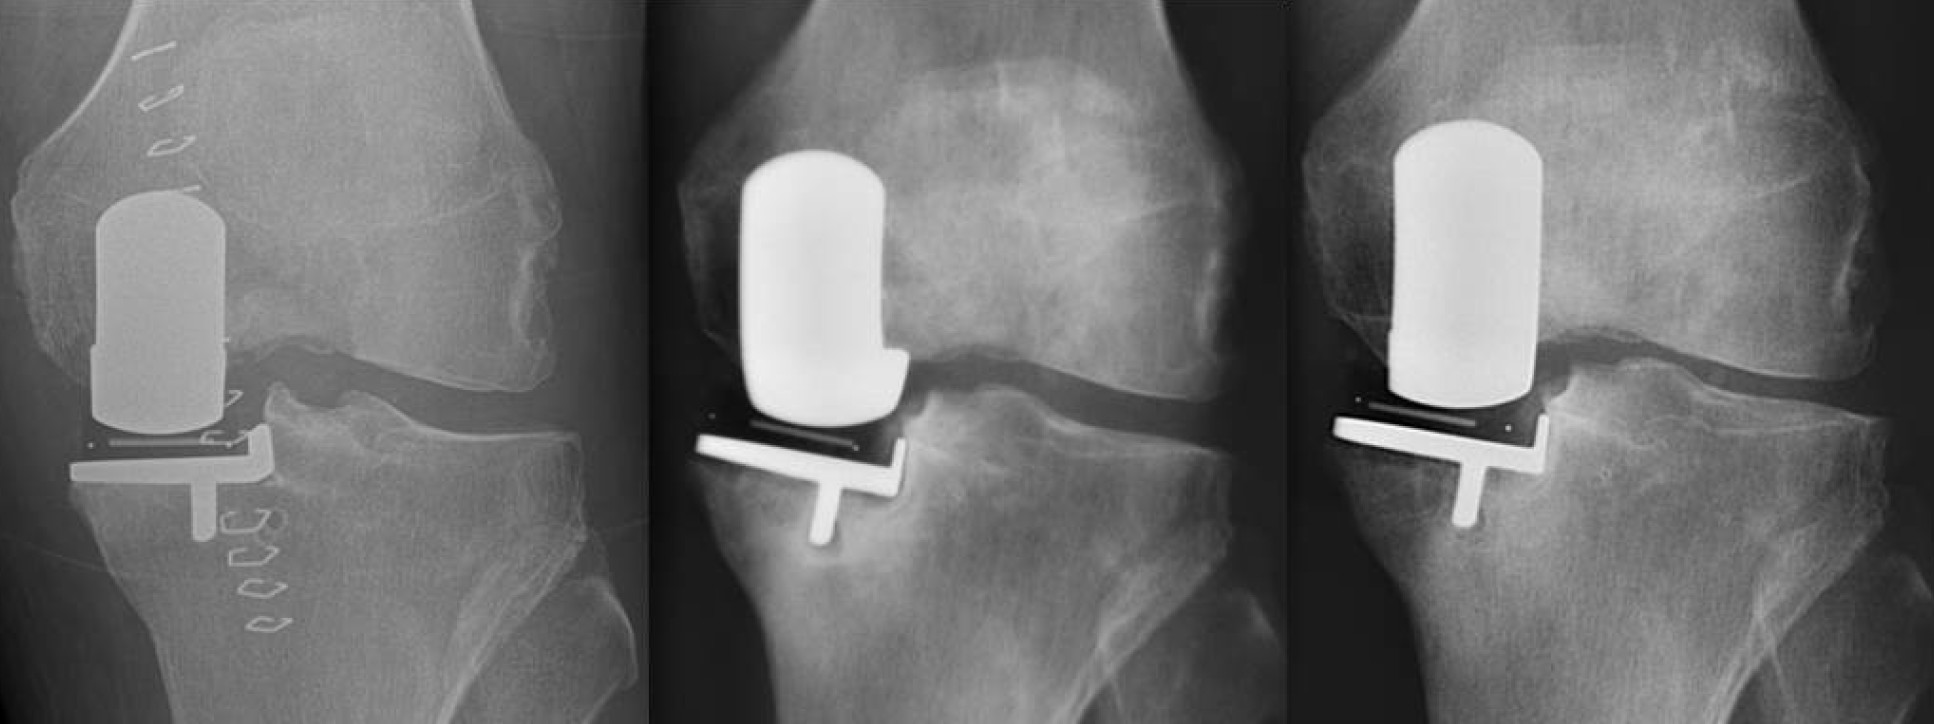

Joint replacement is one of the most common and effective techniques in surgery. There are now over 200,000 hip and knee replacements performed each year in England and Wales, and they are incredibly successful, with high levels of implant survival in the long term and excellent clinical outcomes. However, joint replacement is not perfect. Outcomes after total knee replacement are variable, and up to 20% of patients are dissatisfied with their final result. While complications occur in a small percentage of patients who undergo joint replacement, this still equates to large numbers of patients: around 1,000 patients a month have to undergo revision of their hip or knee replacement in the UK. Our research aims to address these problems from a number of standpoints, working with clinicians and academics in different disciplines both within and outside the Imperial College.

1. Examining routinely collected national and international data to determine the predictors of revision and poor functional outcomes from surgeon, patient, and implant factors, particularly focusing on less invasive interventions such as partial knee replacement, which have a lower rate of serious complications.